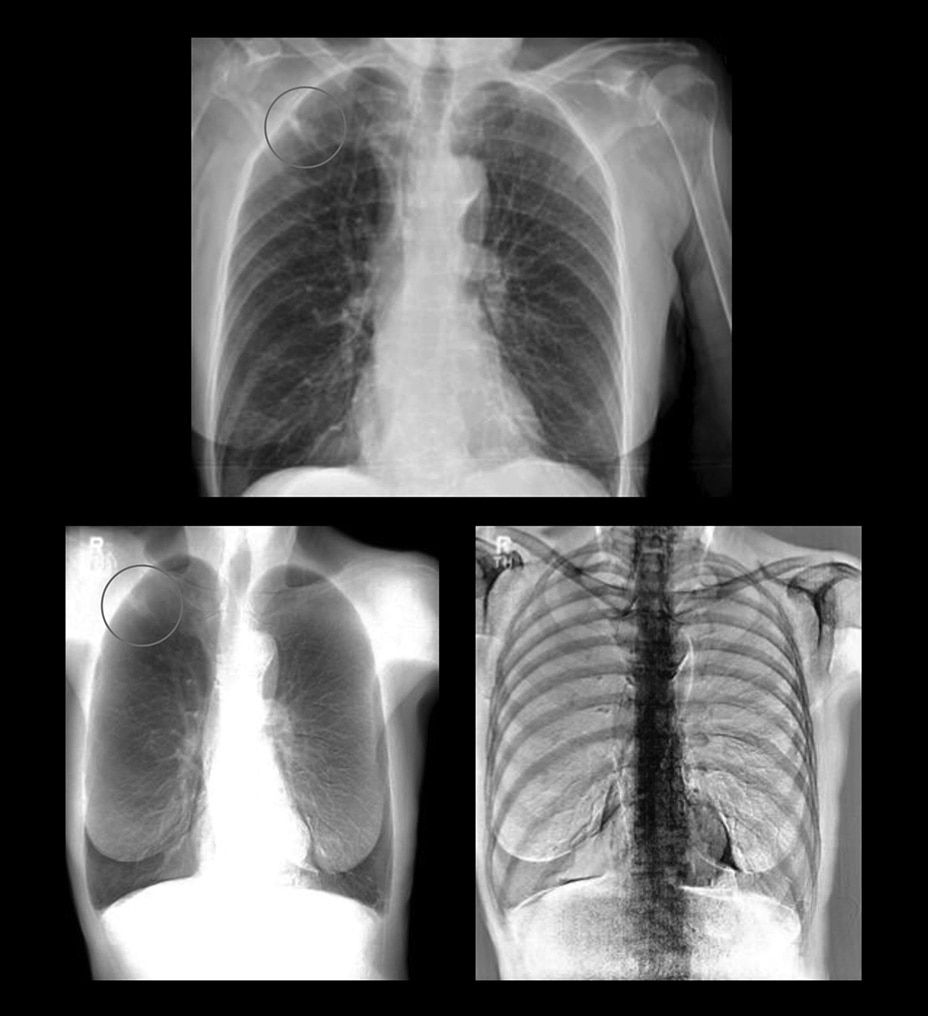

Two acquisitions. Three images.

Rather than relying solely on algorithmic image processing, Dual Energy Subtraction acquires two exposures at different energy levels in less than 160 milliseconds. You can process and view the image as:

• A standard radiographic image

• An image with bones subtracted

• An image of just the bones to highlight foreign objects or calcified structures

These images help you detect abnormalities that may have been obscured in a conventional radiograph.